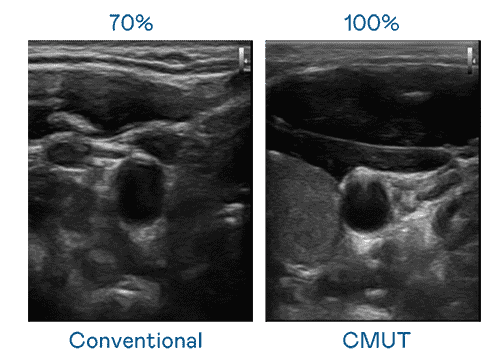

CMUT 技术是一种用电容式微机电元件来产生超音波讯号的技术。。与传统 PZT 压电式技术相比,,,,CMUT 频宽增加 30%,,更宽频的超音波讯号让影像解析度大幅提升,,,是实现高影像品质医疗超音波扫描、、、促进精准医疗发展的关键技术。。。。

超音波影像的解析度高低,,首先取决于探头能发出的讯号频宽。。红龙扑克 CMUT 可提供高清晰的超音波讯号,,提供高频宽、、高灵敏度、、、、影像纹理细节更高的超音波影像,,协助医护人员缩短影像判读时间及利用精准的医疗影像进行诊断。。